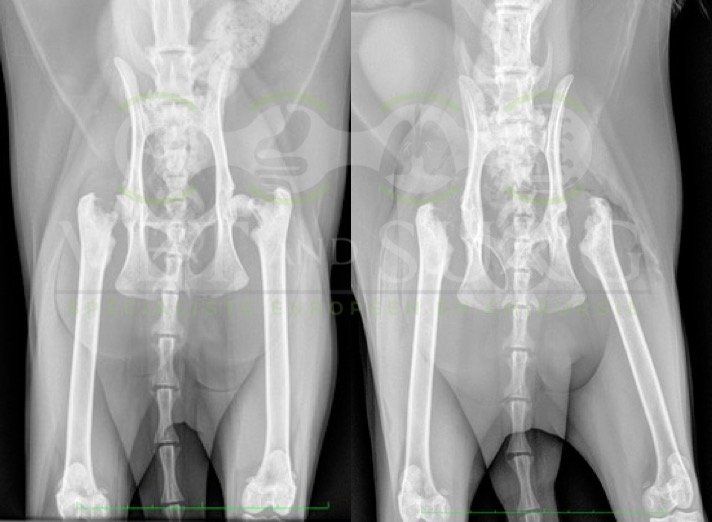

Spike, chaton européen mâle de 10 mois, a été présenté en consultation pour boiterie du membre postérieur droit à la suite d'une chute depuis le 1er étage.

A la radiographie, une fracture de type Salter-harris 1 est diagnostiquée, avec déplacement de l'about discal.